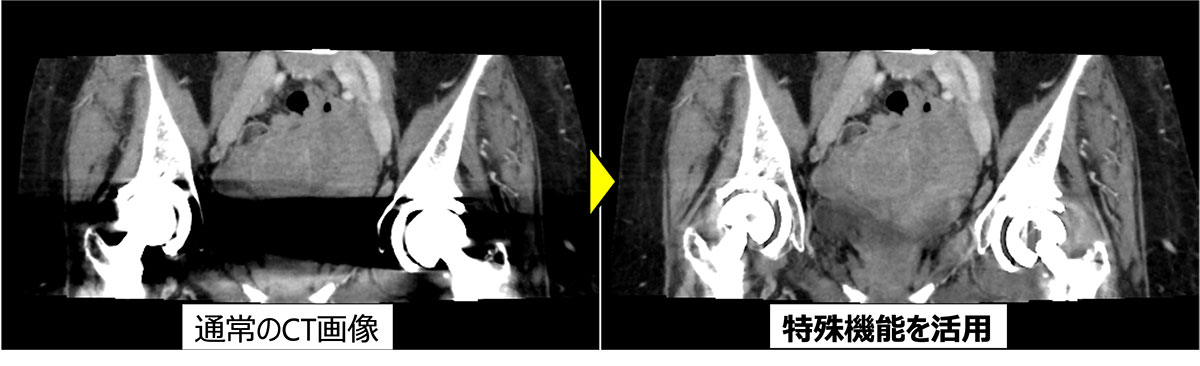

新たなAI技術と特殊機能が多く備わりました。すべてのCT検査に対してAI技術を活用してCT画像の大幅な画質の向上につなげています。さらに画像が劣化する原因となるもの(金属・動き)に対して特殊機能を活用することで、結果の精度と信頼性の向上が期待できます。

お腹のCT画像。股関節に挿入された体内金属により評価できなかった画像を、特殊な処理によって評価可能とした。